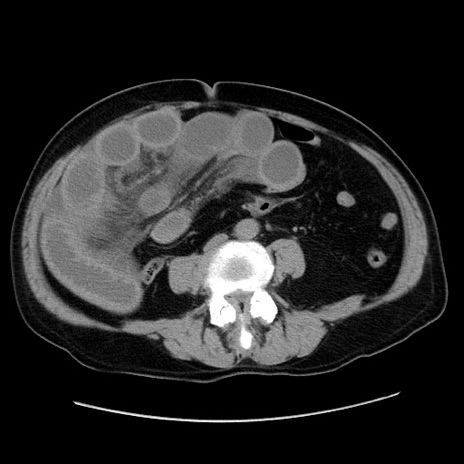

症例30(横断像)

【症例】80歳代男性

【主訴】臍周囲痛

【現病歴】約6時間前から臍下部痛が出現。次第に腹部膨隆・背部痛も生じてきたため来院。背部痛の場所は変化しない。

【身体所見】意識清明、BT 36.3℃、BP  131/87mmHg、P 87bpm、SpO2 100%(RA)、臍周囲自発痛・圧痛あり、反跳痛なし、自発痛部位に一致して板状硬あり、腹部膨隆、腸雑音減弱、CVA tenderness両側陰性。

【データ】WBC 19600、CRP 0.33